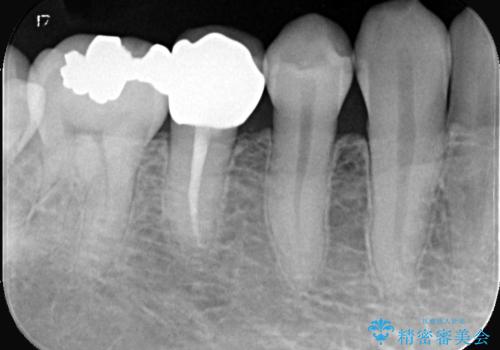

- 虫歯が大きく歯が欠けている状態でした。 そこに食べ物も詰まっている状態でした。

虫歯を除去後、精密根管治療を行い、オールセラミッククラウンで治療を行いました。

虫歯が大きく神経まで到達していました。将来根尖性歯周炎にならないよう徹底的に神経をとり洗浄したうえで被せ物をしています。